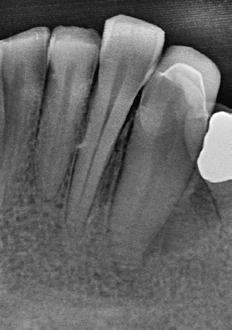

1. ábra: A 15-ös foggyökér meziális felszíne mellett látható radiolucens elváltozás, illetve a felvételen látható a korábban behelyezett gyökértömés, a parapulpális csap segítségével elhorgonyzott csonkfelépítés és a fogat borító cirkonkorona. –2. ábra: A saggitalis irányú CBCT-metszeten jól megfigyelhető az állcsontgerincet elérő radiolucens elváltozás. – 3. ábra: Az axiális irányú CBCT-metszeten egyértelműen látható a kezeletlen palatinális gyökércsatorna, valamint a radiolucens elváltozás mezio-disztális kiterjedése is jól megítélhető. – 4. ábra: A palatinális gyökércsatorna szelektív endodonciai kezelése során először gyógyszeres zárás került behelyezésre. – 5. ábra: A gyógyszeres zárás során alkalmazott kalcium-hidroxid alapú paszta a szulkuszon keresztül a szájüregbe extrudálódott. – 6. ábra: A gyökértömő anyag a középső és apikális gyökéri harmad határán lévő laterális csatornán keresztül a periapikális térbe extrudálódott. 7. ábra: A kezelések befejezését követően 4 évvel készült röntgenfelvételen jól látható a csontállomány gyógyulása és a fiziológiás gyökérhártyarés újbóli kialakulása. –8. ábra: A peroperatív CBCT-felvétel alapján készített koronális irányú metszeten jól látható a gyökércsúcs körül lévő periapikális felritkulás. – 9. ábra: A kezelések befejezése után 4 évvel készített CBCT-felvételen a gyulladásos lézió teljes megszűnése észlelhető.

A CBCT-készülékek endodonciai alkalmazásának talán az az egyik legnagyobb előnye, hogy így olyan anatómiai struktúrák is láthatóvá válnak, amelyeket egyébként nem tudnánk detektálni panoráma, cephalo, vagy periapicalis felvételek segítségével. Mivel a CBCT-felvételek kiértékelése számítógép segítségével történik, így a felvételek vizsgálata során lehetőségünk van az adott területet több nézőpontból és több síkban is megvizsgálni. 2015 októberében egy korábban a rendelőnkben kezelt 55 éves férfi páciens azzal a céllal kereste fel ismét a rendelőnket, hogy másodvéleményt kérjen egy jobb felső kvadránsban található fogával kapcsolatban. Egy másik rendelőben történő vizsgálat során a panaszos fog törését vélelmezték és a fog eltávolítását javasolták, illetve arról is beszámolt, hogy az elmúlt hét során ezen a területen egy puha duzzanat is kialakult. A klinikai vizsgálat során a jobb felső első és második kisőrlő között (14–15) egy fluktuáló duzzanatot észleltünk az áthajlásban. Az 15-ös fog mesialis oldalán 12 mm mély tasakot szondáztunk. A páciens által hozott periapicalis felvételen a 15-ös fog gyökércsúcsának mesialis részén egy nagy kiterjedésű radiolucens elváltozás volt észlelhető (1. ábra). A saggitális síkban vizsgált CBCT-felvételen (Carestream CS 9000, Carestream Dental) a lézió valódi kiterjedése is láthatóvá vált (2. ábra). A megelőző endodonciai kezelések során csupán a bukkális csatorna került detektálásra és gyökértöméssel való ellátásra. Az axiális irányú CBCT-szeleteken egyértelműen látható volt az ellátatlan palatinális gyökércsatorna (3. ábra)

Először kalcium-hidroxid alapú ideglenes gyógyszeres zárás került a palatinális csatornába (UltraCal XS, Ultradent Products; 4–5. ábra), amelyet 6 hét után a végleges gyökértömés elkészítése előtt eltávolítottunk. A gyökértömés elkészítése során meleg vertikális kondenzációs technikát alkalmaztunk. Radiológiai felvételen megfigyelhető volt, hogy a gyökértömő anyag egy laterális csatornán keresztül kis mennyiségben a periapicalis térbe extrudálódott (6. ábra). A 4 évvel később készített kontrollfelvételeken a lézió gyógyulása volt megfigyelhető (7–9. ábra). A vizsgálati eredmények és a kezelés kimenetele egyértelműen igazolta, hogy nem gyökérfraktúrával álltunk szemben, tehát a kezdeti diagnózis tévesnek bizonyult. Ez is azt erősíti, hogy korlátozott mennyiségben rendelkezésre álló adatok alapján nem lehet pontos diagnózist felállítani. Manapság szinte elengedhetetlen a CBCT-felvételek endodonciai beavatkozások során történő használata, feltéve, ha ezek elkészítése során az ALARA elv (as low as reasonably achievable) betartásra kerül.